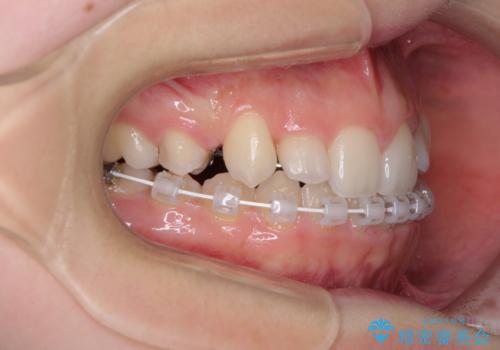

目立つ八重歯を目立たない装置で ハーフリンガルによる抜歯矯正

- 矯正装置

- ハーフリンガル

- 前歯のデコボコと八重歯を気にして来院された患者様です。

目立たない装置を希望されたので、上顎が裏側装置のハーフリンガルを選択し、左右上顎小臼歯1本ずつを抜歯して、矯正治療を行うこととしました。